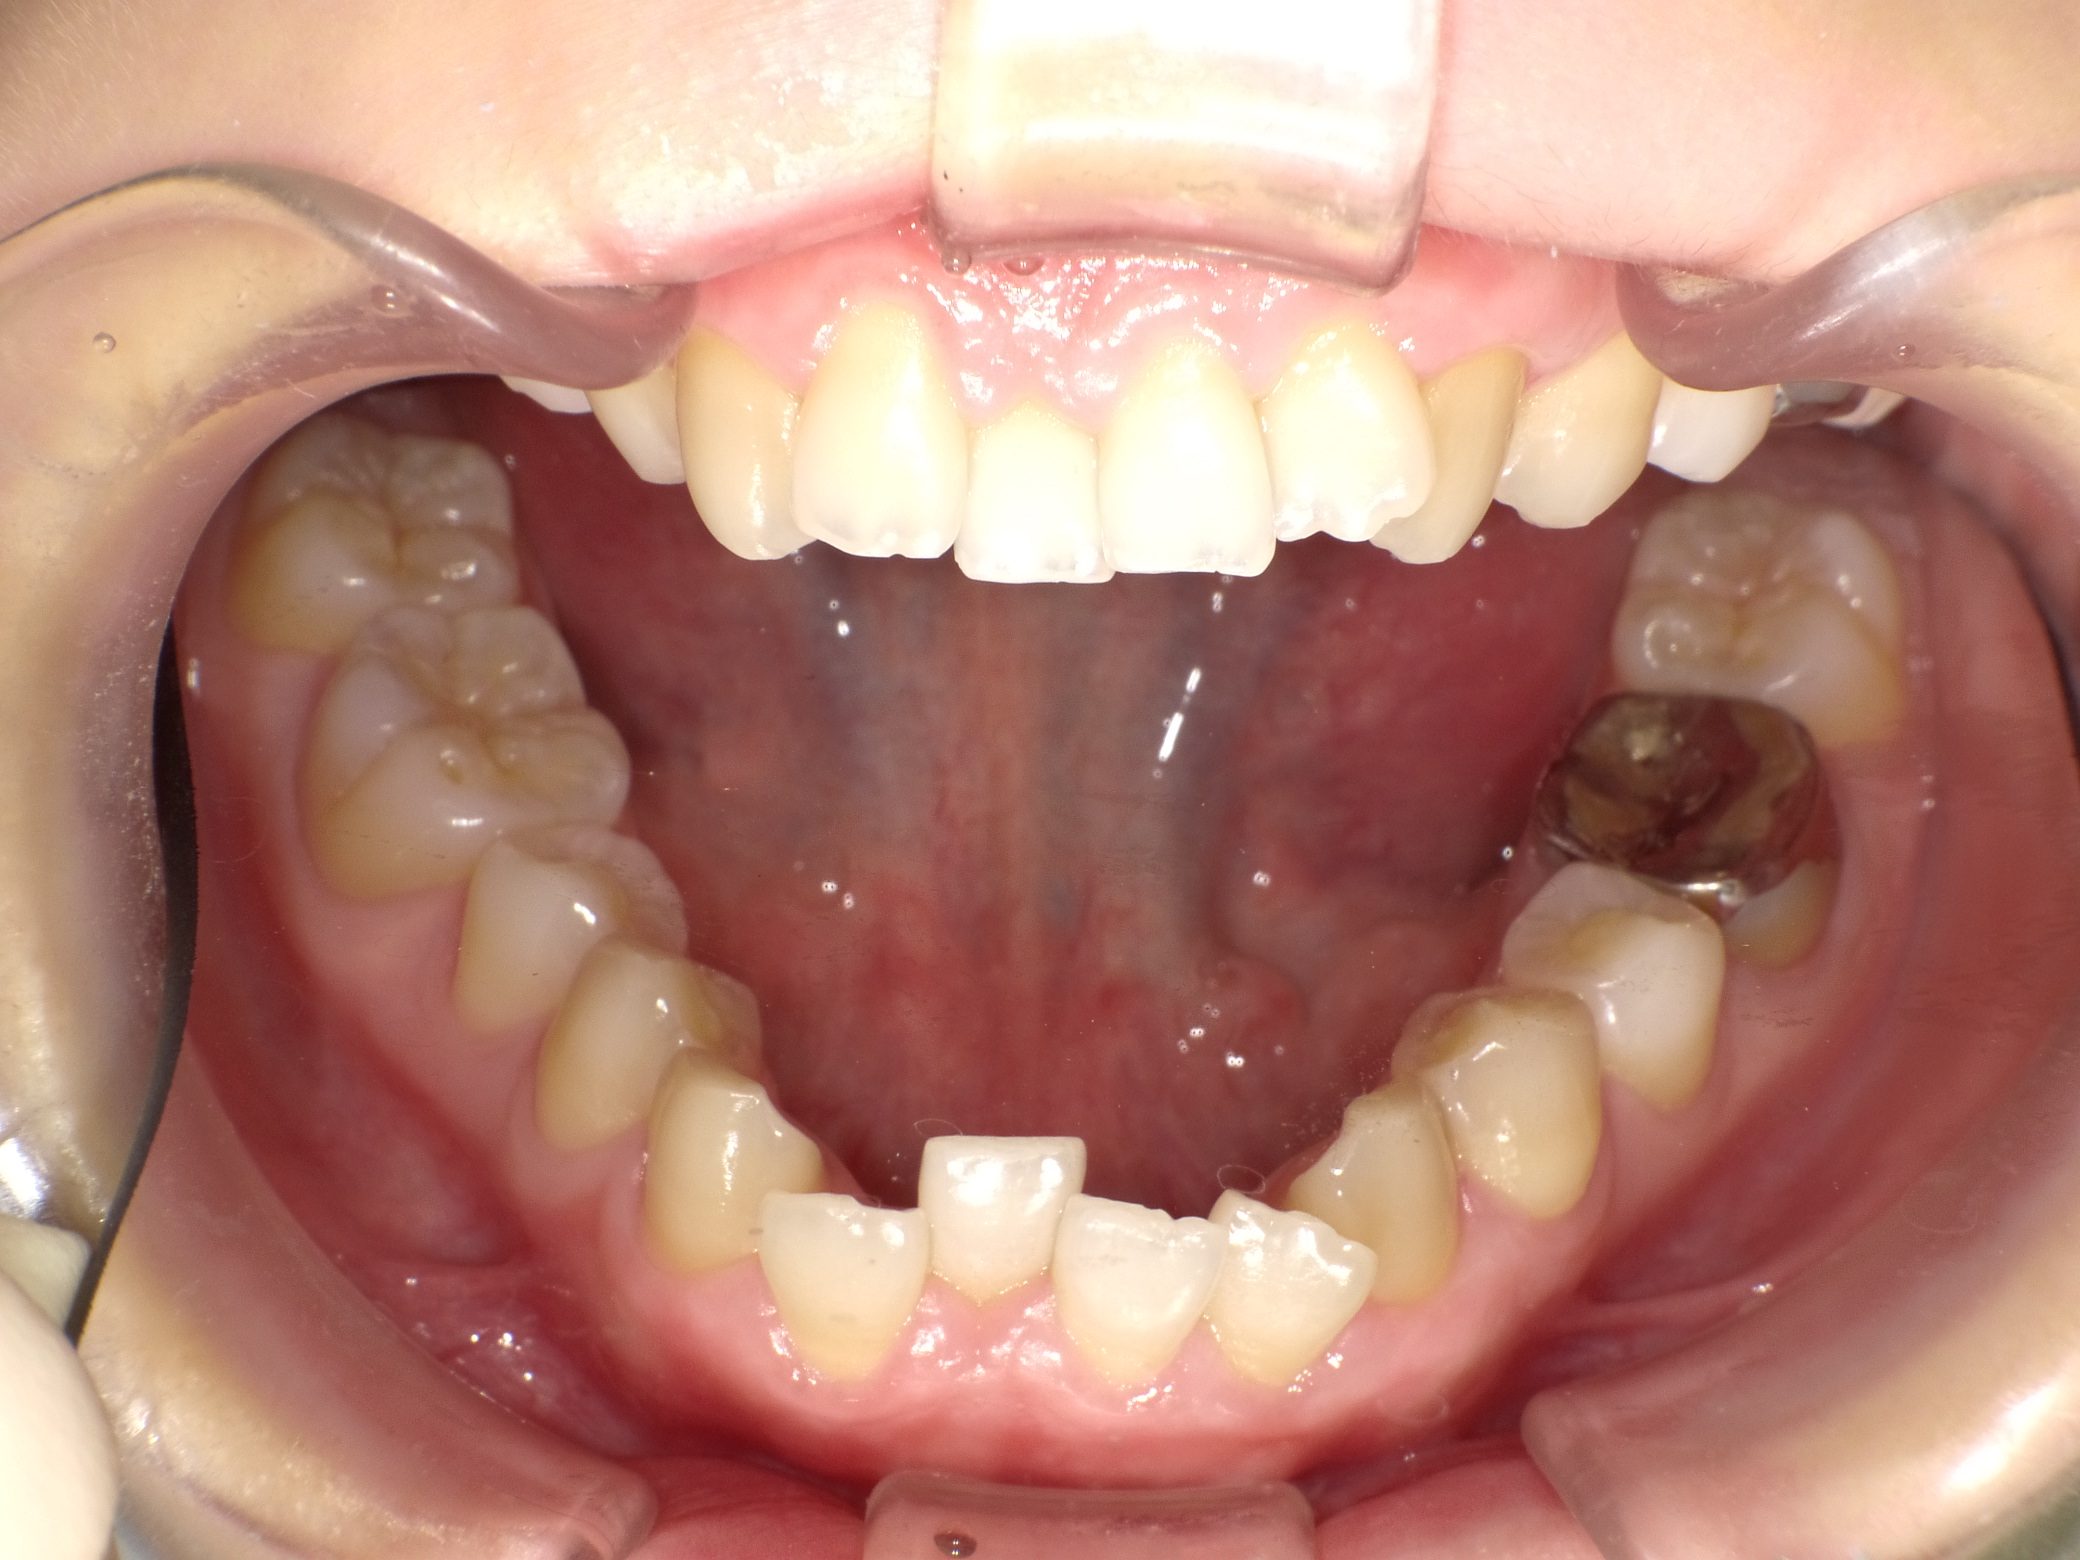

【大学生】インビザラインフル 叢生(ガタガタ)を改善

インビザライン フル

でこぼこ

非抜歯

2期治療のみ

治療期間

3年

治療開始

21歳

種類

インビザラインフル

費用

55万円(当時)現在だと66万円のプランです

使用装置

インビザライン

コメント

途中で県外に転居があり、なかなか通院できなかったため、期間が延びてしまいましたが、しっかり取り組んでくれました。

ご兄弟も矯正してくれています。